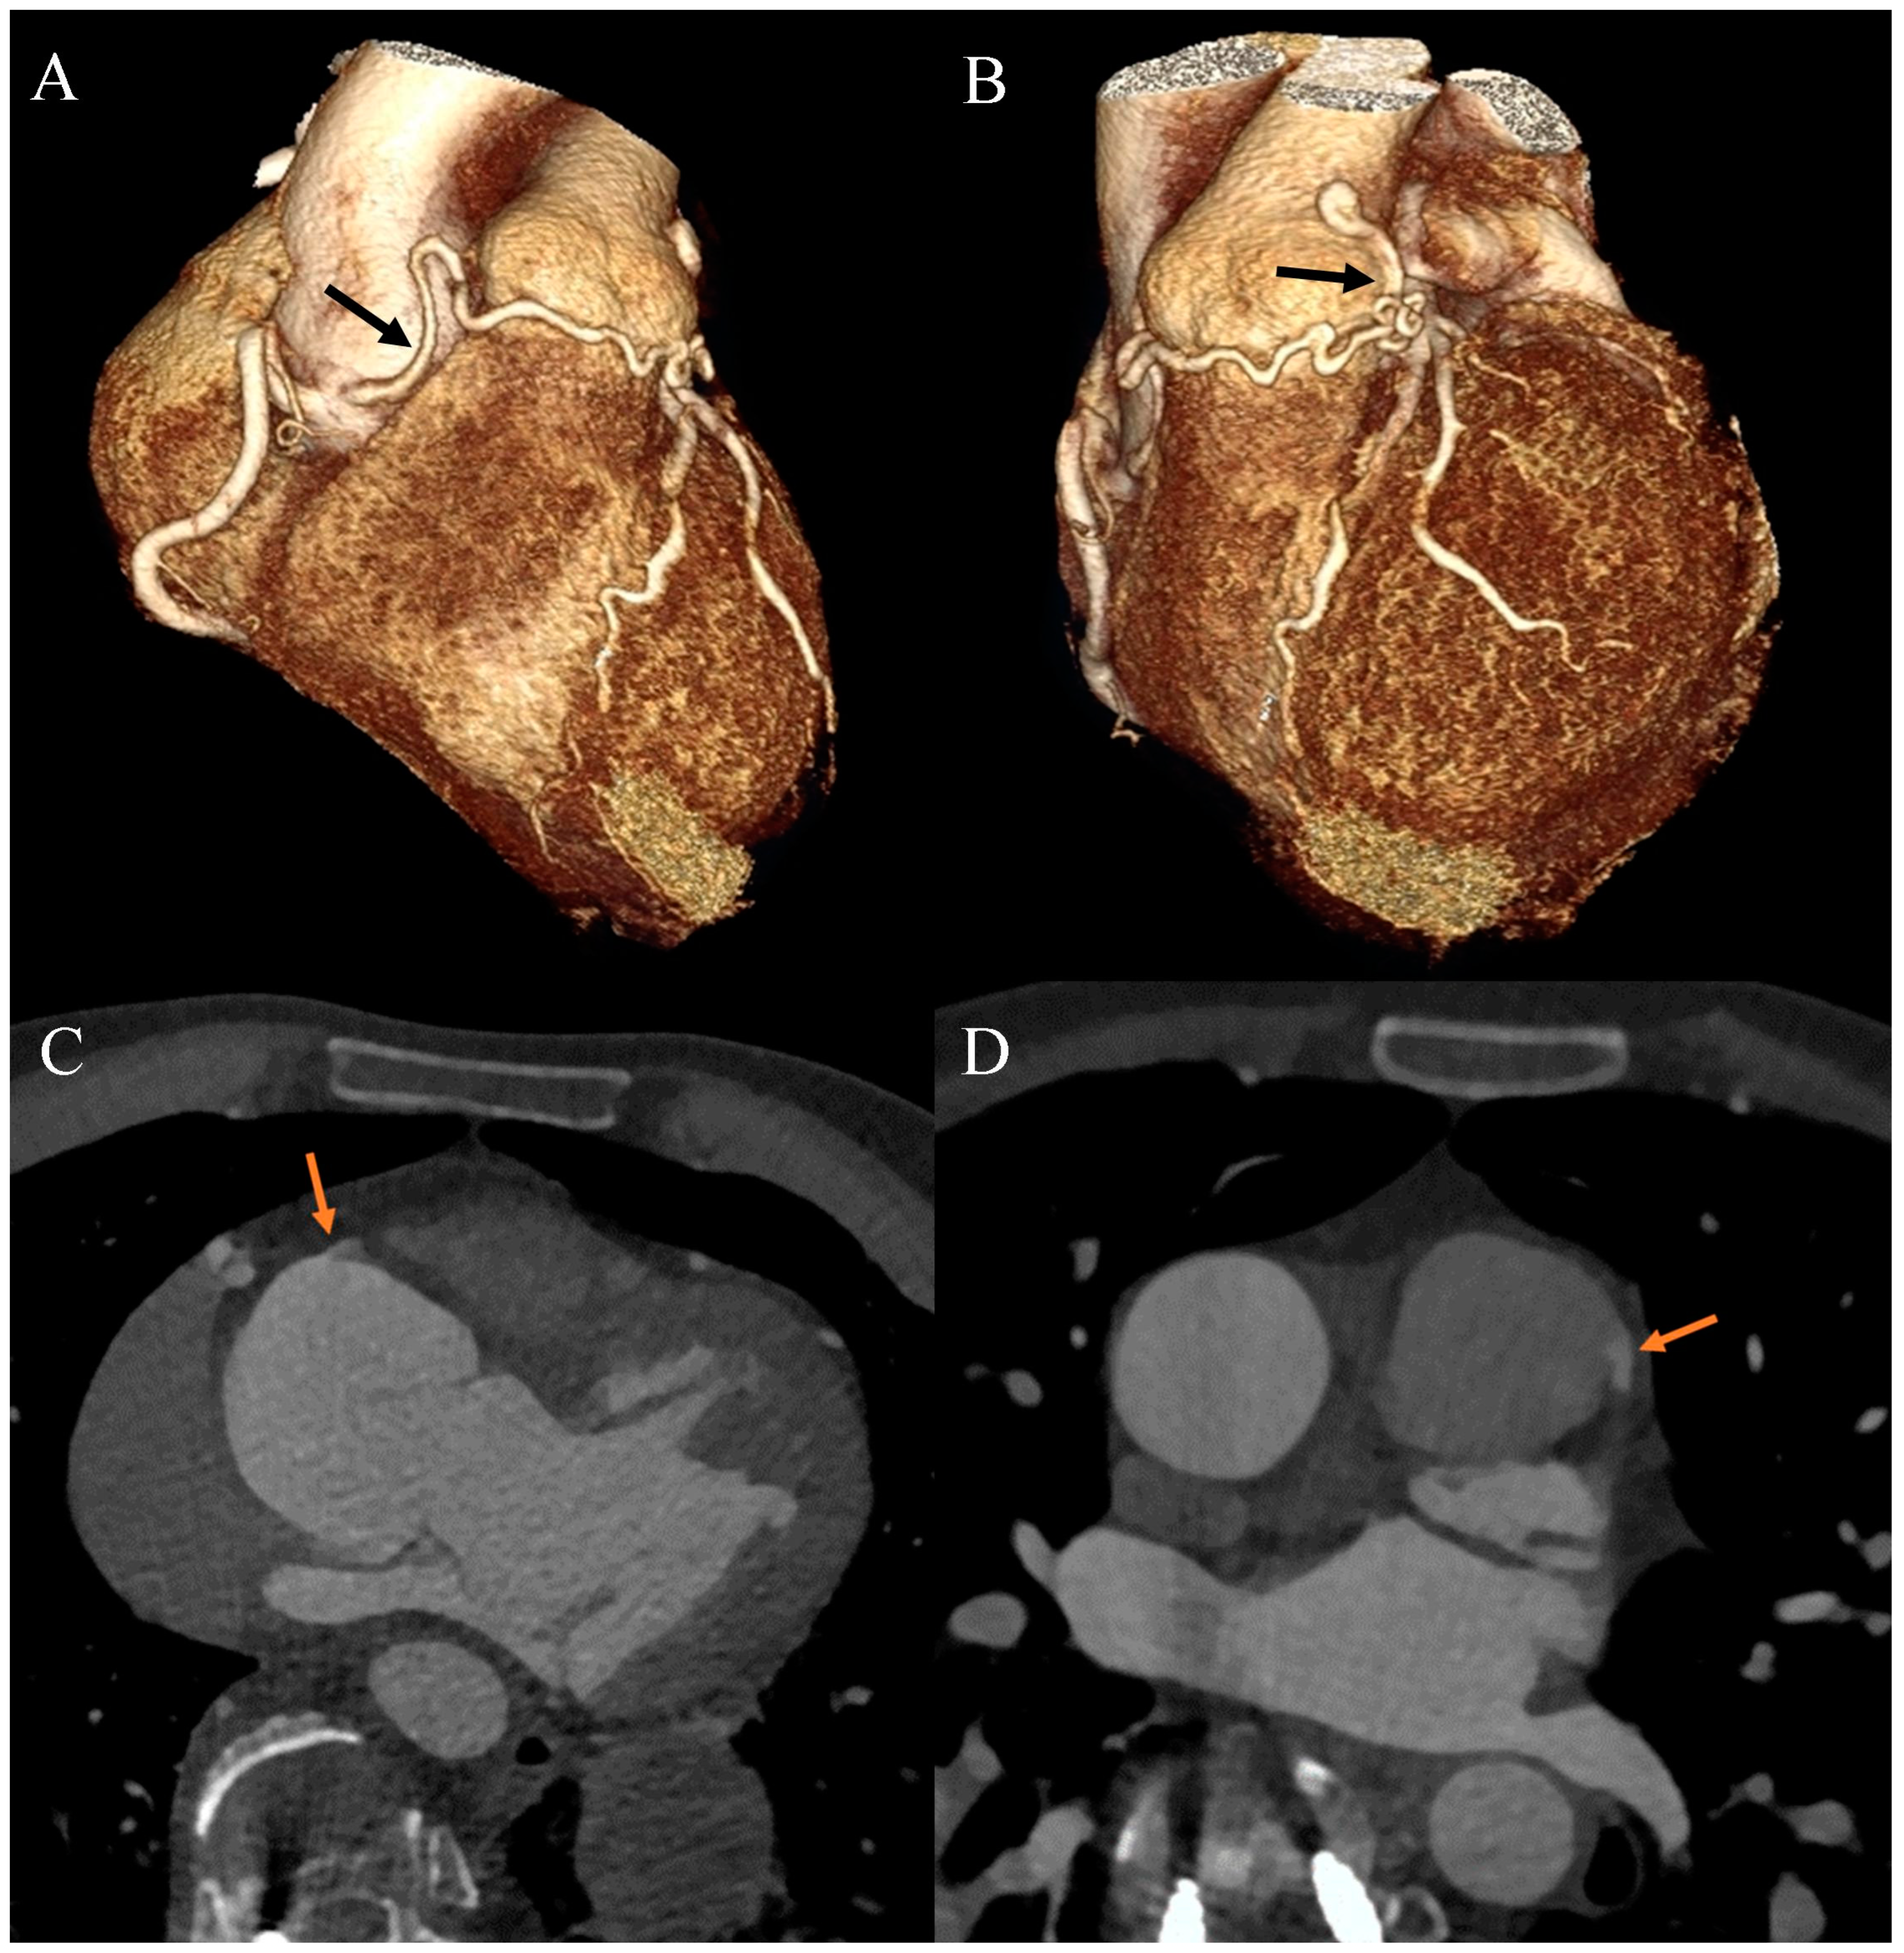

Ehlers–Danlos syndrome (EDS) encompasses a spectrum of heterogeneous, heritable disorders affecting connective tissue. According to the 2017 international classification of EDS, there are 13 subtypes. A rare 14th subtype was found in 2018. Each subtype has unique aspects, and a genetic cause has been identified in all subtypes except hypermobile EDS [1]. Clinical manifestations arise from the pervasive fragility and weakness of the soft connective tissue. Apart from manifestations in the skin, ligaments, joint and internal organs, there are subtypes of EDS which affect blood vessels and cardiac valves. These subtypes confer a higher risk of cardiac valve insufficiency, aneurysms, dissections, or ruptures of arteries, including coronary ruptures [2]. The estimated prevalence of EDS approximates 194.2 cases per 100,000 individuals [3]. Here, we present a case of a 34-year-old man with normal body weight, with hypermobile EDS, type 2 diabetes mellitus, chest deformity, aortic valve regurgitation, and aortic bulb aneurysm characterized by an axial diameter measuring approximately 5 cm (Figure 1). The patient had severe rotational scoliosis of the Th-L spine, with a significant deepening of the thoracic kyphosis and lumbar lordosis. There was a decrease in the AP dimension of the chest, a deformation of the ribs with a decrease in the width of some intercostal spaces, and a secondary widening of the width of other intercostal spaces. The patient underwent elective spine surgery to correct severe rotational scoliosis of the T-L spine. After postoperative rehabilitation, the patient underwent a thorough assessment of eligibility for aortic bulb aneurysm and aortic valve replacement surgeries. Consequently, a coronary computed tomography angiography (CCTA) was performed five months after the spinal surgical intervention. The CCTA revealed an absence of the left main (LM) and the right coronary artery (RCA) dominance. Significantly, the left circumflex artery (LCx) exhibited an ectopic origin from the right sinus of the valsalva, demonstrating a retroaortic course in the proximal segment and a typical course in the distal segments (Figure 2). Furthermore, the presence of a coronary–pulmonary arterial fistula (CPAF) in the CCTA was visualized. A vessel with an approximate diameter of 0.3 cm originated from the right sinus of the valsalva and progressed anteriorly and then towards the left, traversing anteriorly to the right ventricular outflow tract. Thereafter, this vessel was visible to the left of the main pulmonary artery, ultimately divided into multiple narrow segmentally aneurysmally dilated and tortuous fistula vessels. The fistula vessels showed communication with the proximal segment of the main pulmonary artery (Figure 3). Moreover, the imaging revealed the presence of an additional right pulmonary vein (Figure 4). The CCTA revealed calcifications within the aortic valve. The patient received a qualification card for surgical treatment, was informed about the high surgical risk, and is awaiting the operation.

Figure 1. Thoracic aorta computed tomography angiography. Aortic bulb aneurysm. (A). Multiplanar reconstruction. View parallel to the aortic annulus plane. Subsequent measurements were made between the commissures of the aortic valve leaflets and the midpoints of the aortic valve leaflets. (B). Multiplanar reconstruction. Perpendicular view to the aortic annulus plane in the long axis. The designations (1–6) indicate subsequent measurements: aortic annulus—3.01 cm (5); aortic bulb—4.79 cm (1), 5.01 cm (2), 4.81 cm (3), 4.97 cm (4); sinotubular junction—4.28 cm (6).